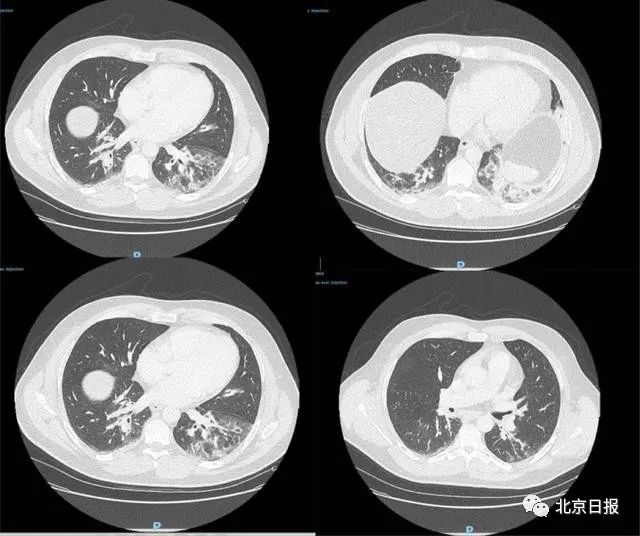

据了解,患者去年12月27日到急诊室就医,CT检查显示双侧肺下叶呈现磨玻璃影,并伴有咯血、咳嗽、头痛及发热症状,且当时症状已持续4天。病患当天被收入重症监护室并接受抗生素治疗,后因病情好转于12月29日解除重症监护。

图为病患CT检测影像

据此证明,新冠病毒已于2019年12月底在法国传播,比该国官方所称于1月24日首次发现病例,提早了一个月。由此也可推测,在2020年1月期间法国或存在大量无症状感染者,他们造成了病毒的进一步扩散。